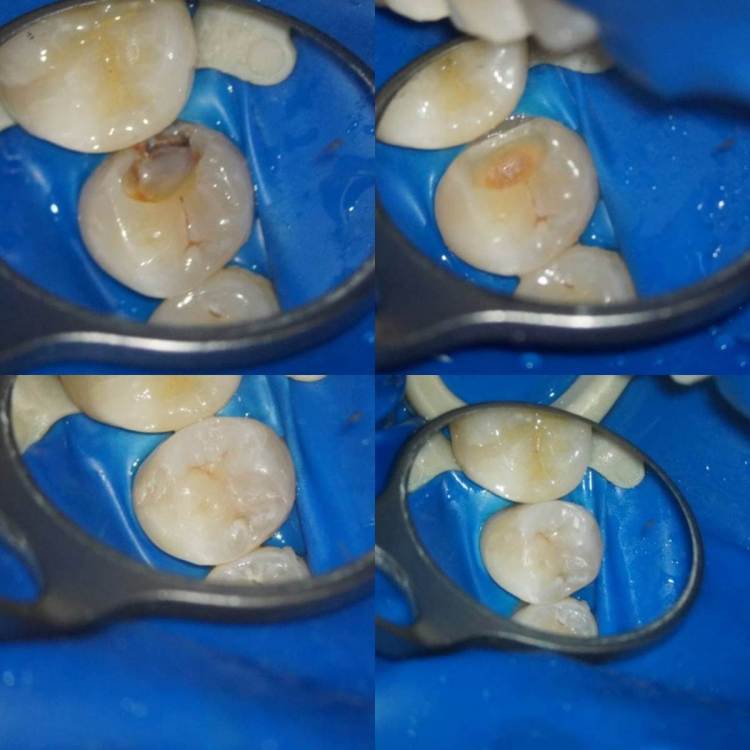

1586Doc Опубликовано 25 декабря, 2021 Автор Поделиться Опубликовано 25 декабря, 2021 (изменено) ну и пломбировка 46 зуб, далее 6-12 месяцев ожидания. Изменено 25 декабря, 2021 пользователем 1586Doc 1 2 Ссылка на комментарий